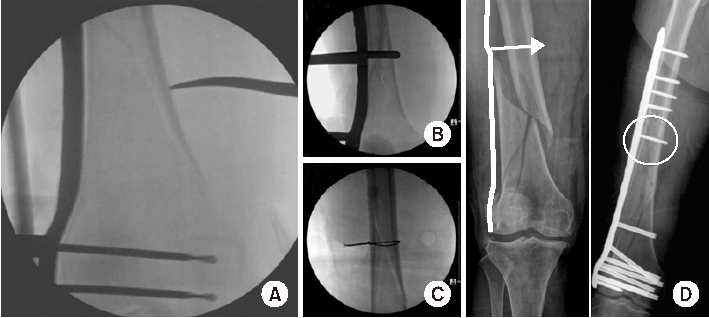

Fig. 8

(A) Schematic diagram showing the axial shape of the distal femur and the protrusion of distal locking screw. (B) True anteroposterior radiograph showing that the lengths of the distal locking screws appear to be appropriate. (C) Radiograph taken after rotating a thigh approximately 25° internally, showing the protrusion of multiple screws across the medial cortex.